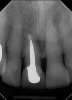

Fig 3. In a separate case, radiograph of a decayed endodontically treated tooth is shown. The decision was made to extract it before further damage to adjacent teeth and/or loss of bone could occur.

Figure 3